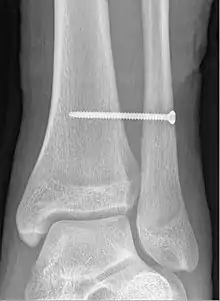

X-ray of a syndesmotic screw in place.

A syndesmotic screw designed to replace the inferior tibiofibular articulation that fix the tibia and fibula together at the lower joint, is 5–6 cm long and made of a stainless, solid metal.